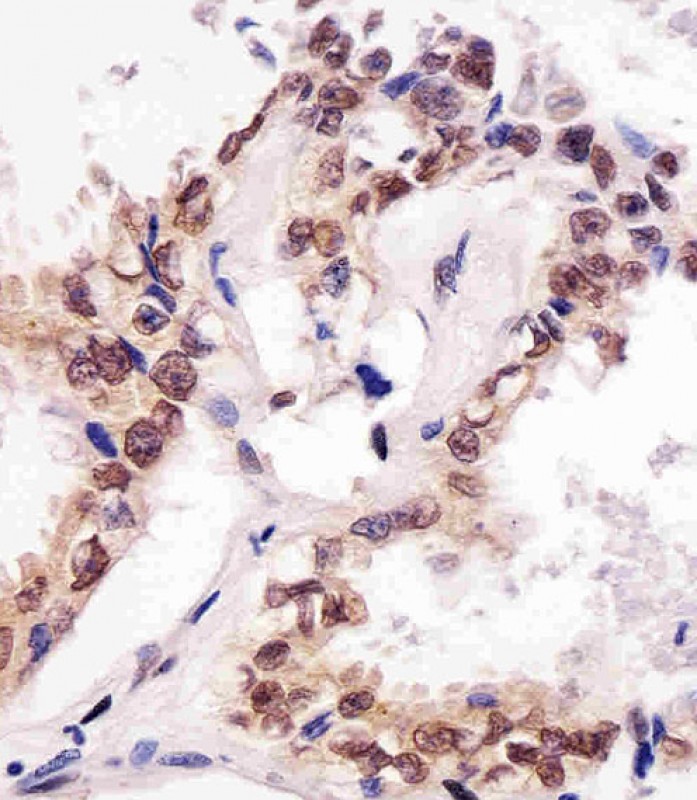

P33128 staining SUMO1 in human lung adenocarcinoma tissue sections by Immunohistochemistry (IHC-P - paraformaldehyde-fixed, paraffin-embedded sections). Tissue was fixed with formaldehyde and blocked with 3% BSA for 0. 5 hour at room temperature; antigen retrieval was by heat mediation with a citrate buffer (pH6). Samples were incubated with primary antibody (1/25) for 1 hours at 37°C. A undiluted biotinylated goat polyvalent antibody was used as the secondary antibody.

P33128 staining SUMO1 in human breast carcinoma tissue sections by Immunohistochemistry (IHC-P - paraformaldehyde-fixed, paraffin-embedded sections). Tissue was fixed with formaldehyde and blocked with 3% BSA for 0. 5 hour at room temperature; antigen retrieval was by heat mediation with a citrate buffer (pH6). Samples were incubated with primary antibody (1/25) for 1 hours at 37°C. A undiluted biotinylated goat polyvalent antibody was used as the secondary antibody.